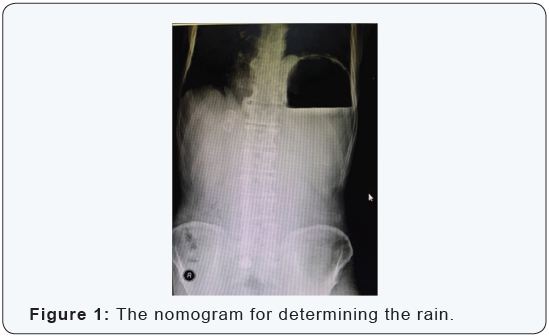

Nasogastric tube decompression was planned but not succeeds despite 3 attempts. Posteroanterior chest and direct abdominal X-ray revealed expanded mediastinum, elevated left diaphragm and left sided increased gastric gas (Figure 1). Computerized abdominal tomography screening revealed left thoracic shifting of extremely dilated stomach. Also, atypical replacement of pylorus and fundus was indicating to gastric volvulus (Figure 2). The patient was hospitalized with gastric volvulus diagnosis and preoperative resuscitation with fluid rehydration initiated. At the operation, surgical exploration through median incision revealed that extremely dilated stomach filled the half of abdomen and rotated almost 180 degrees around the small curvature - big curvature axis (mesenteroaxial volvulus) (Figure 3). Also, pylorus and fundus were herniated to left thorax through a 20x10 cm defect located left lateral side of left diaphragmatic crus as is shown in radiological investigations.